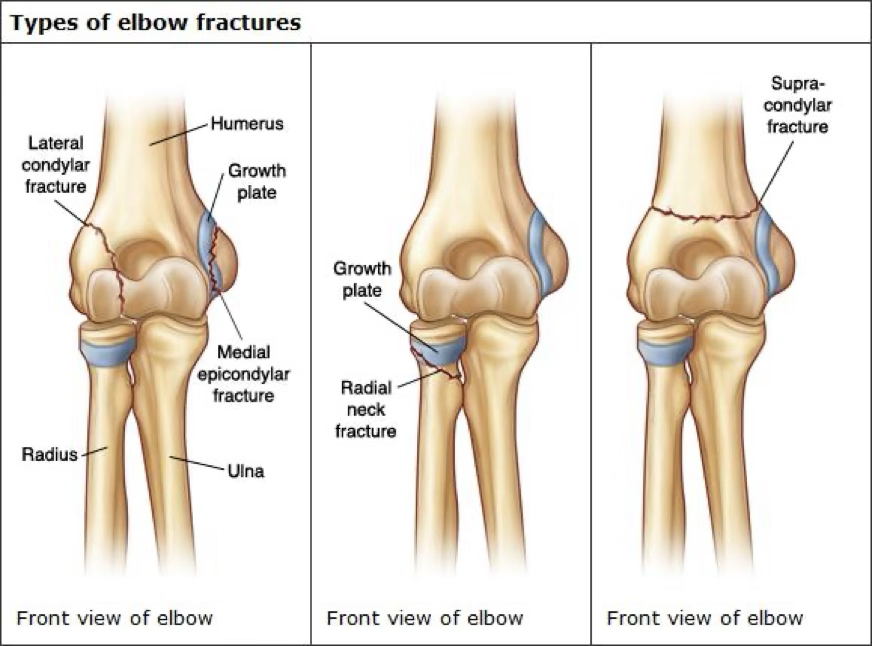

elbow fracture

FOOSH mechanism or direct hit

possible even incorrect reduction with elbow

symptoms: swelling, muscle spasm, pain, possible deformity, reduced ROM, compromised neurovascular

treatment: stabilize and ship

may need a sling or cast, or surgery

treatment will depend on cast vs. surgery